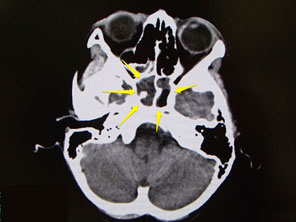

われるような目の辺りの痛みで眠れないとの訴えで来院された、子供さんです。

CTで蝶形骨洞に陰影があり、服鼻腔炎による痛みも考えられ、抗生剤の点滴を受けられました。

約2ヶ月程度、内服での副鼻腔炎の治療を行い、蝶形骨洞炎が消えたのを確認しました。